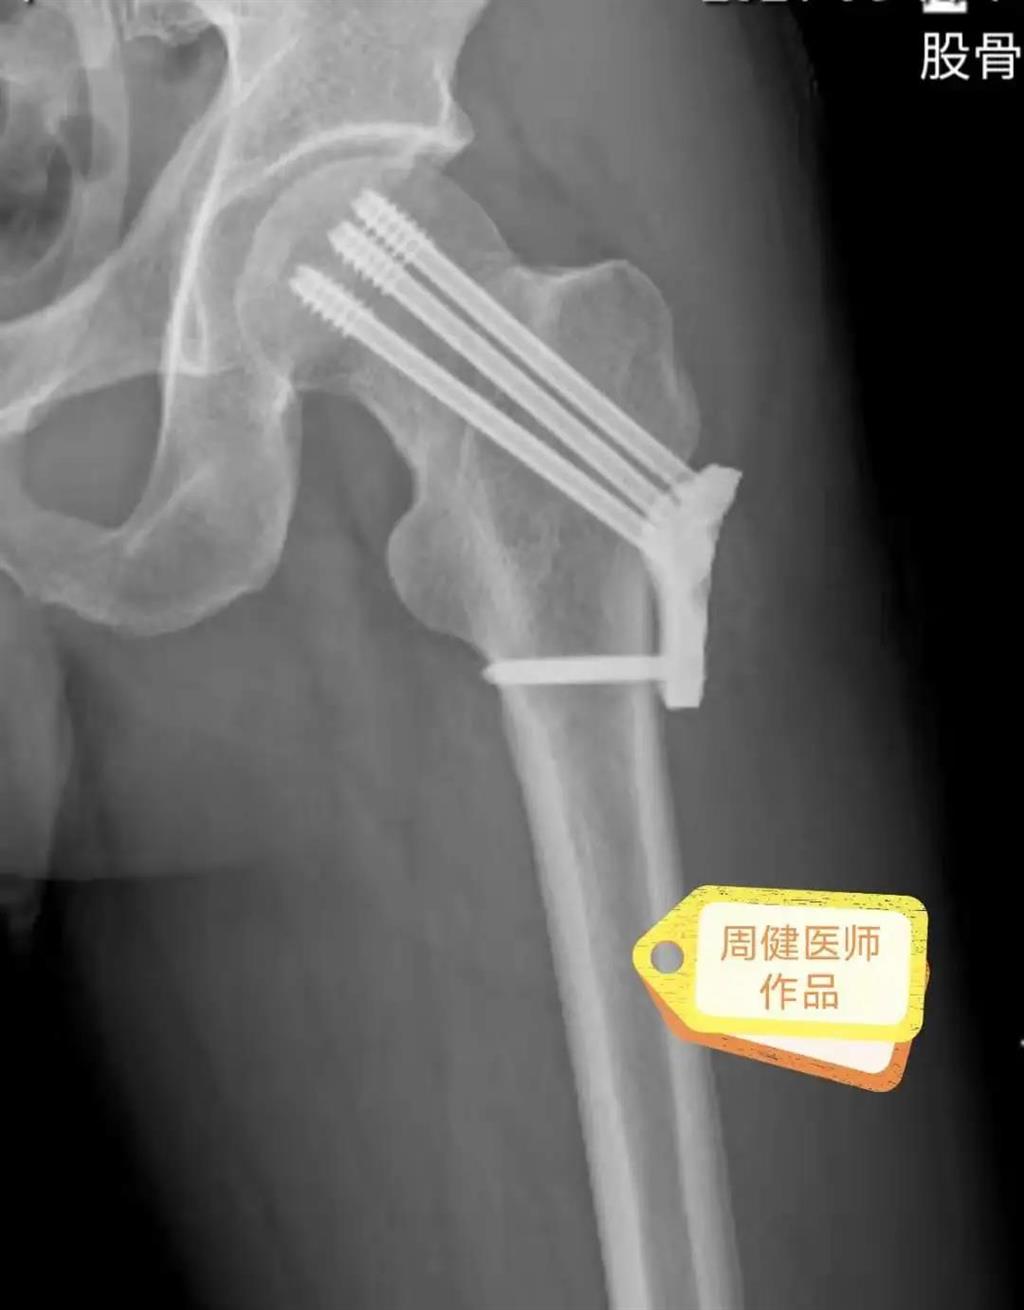

6月30日的“關(guān)節(jié)置換術(shù)”,患者是一位上了年紀(jì)的老人,苦于病痛折磨多年的他四處“求醫(yī)問藥”,最后在多位專家醫(yī)師及病友地力薦下選擇了和平國際醫(yī)院,在醫(yī)師團隊“偷天換日”般的手術(shù)后,老人成功告別了苦纏多年的病痛。

周健說,這場“關(guān)節(jié)置換術(shù)”對于他們團隊而言其實算是比較普通的手術(shù),因為做過很多同類的手術(shù),成功案例繁多,因此在手術(shù)操作上有較多地實操經(jīng)驗。“不過話雖如此,作為醫(yī)生我們對于每一場手術(shù)都會全力以赴,這是為醫(yī)者的職責(zé)也是義務(wù)。”